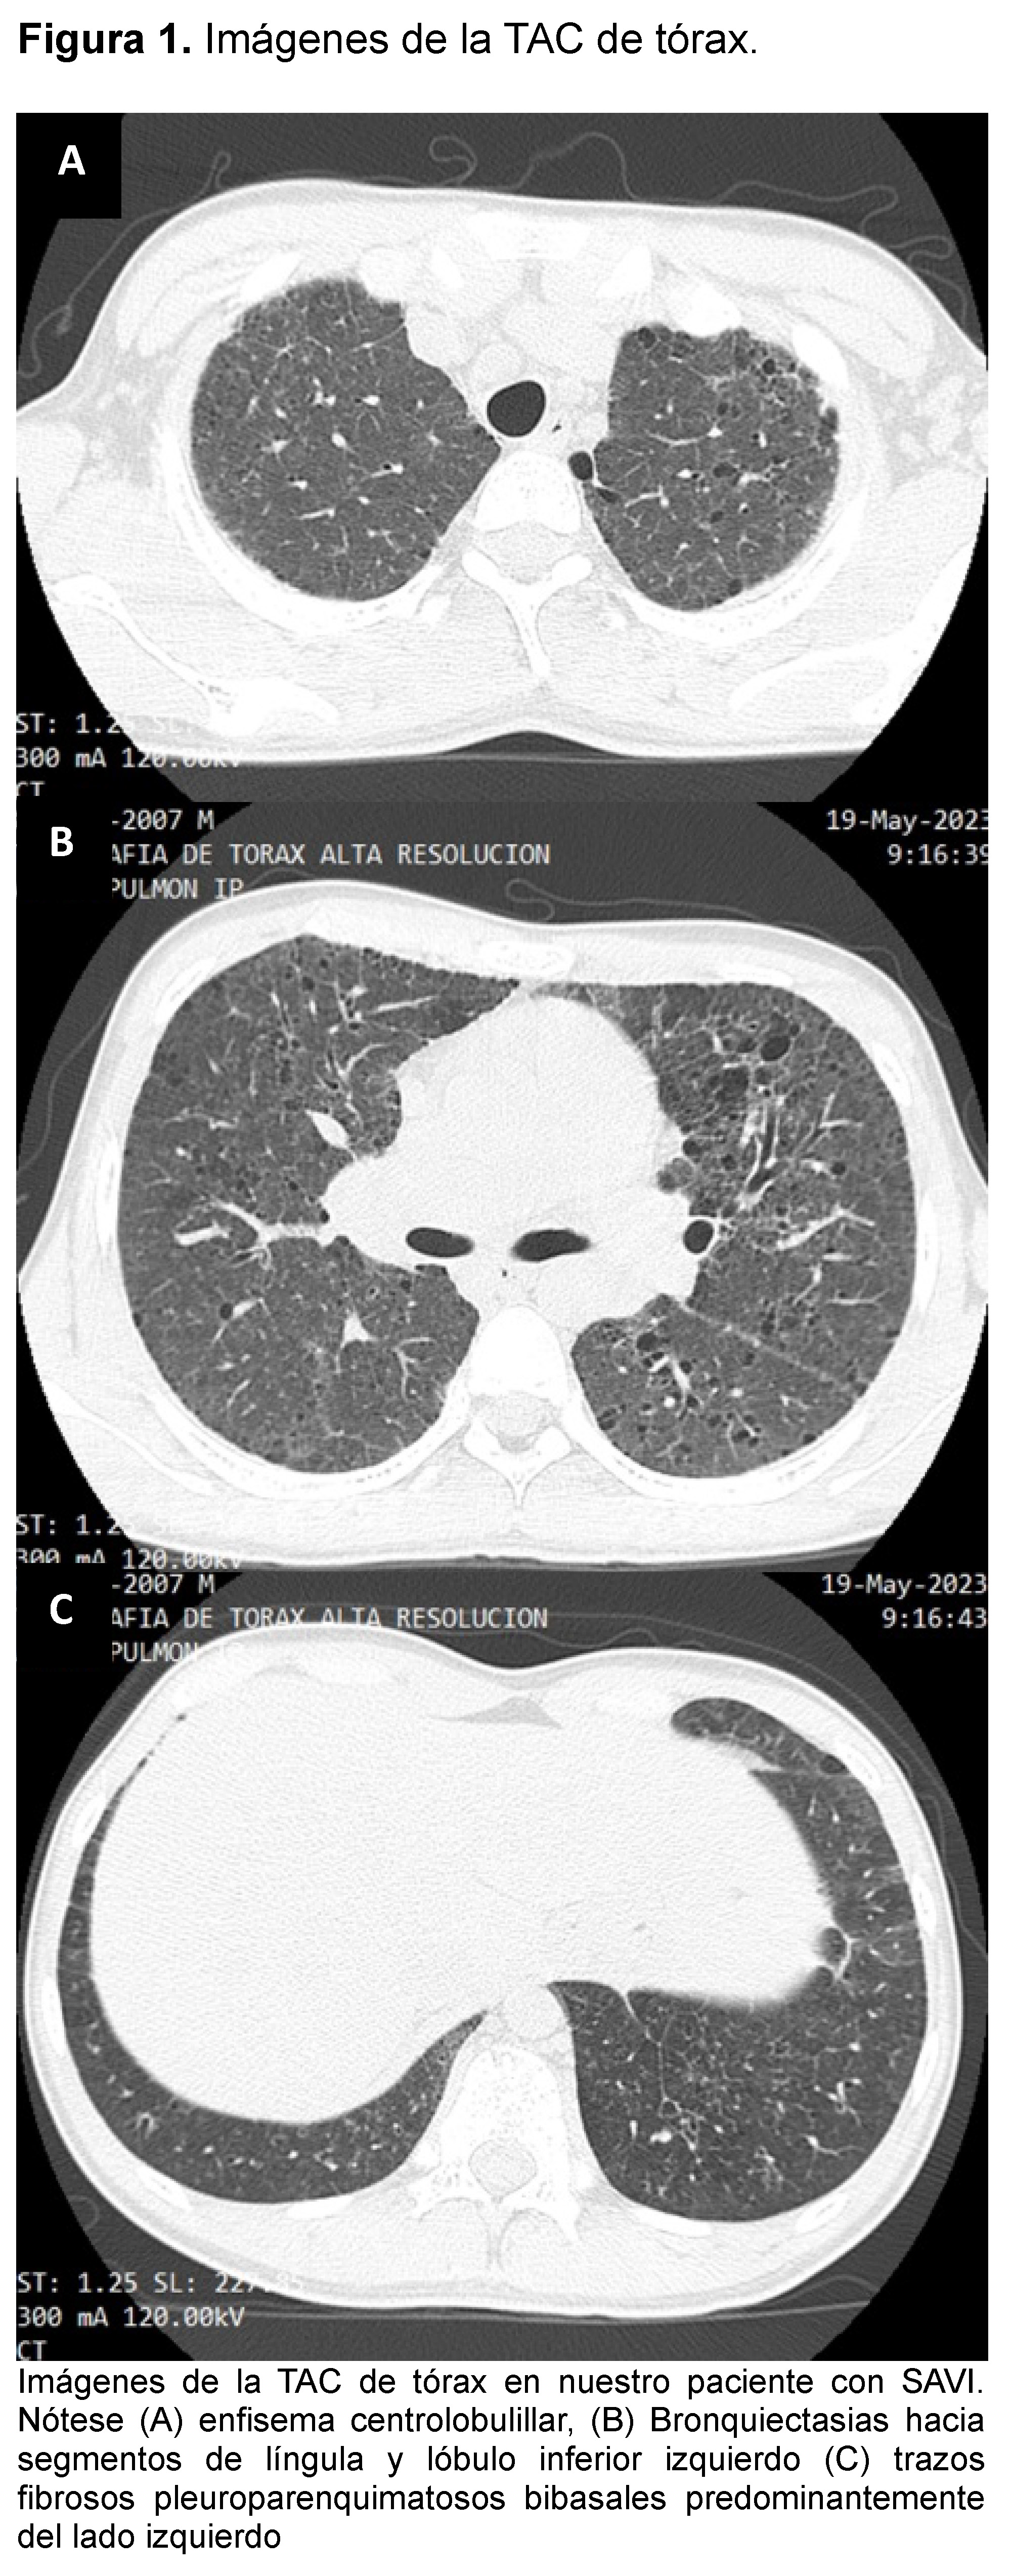

At 15 years of age, after SARS-CoV-2 infection, the frequency and severity of crises increased. Simple spirometry and post bronchodilator was indicated and resulted in severe obstruction with non-significant bronchodilator testing. A chest CT scan was performed, which revealed central acinar pulmonary emphysema, bronchiectasis in the basal middle segment of the lower lobe of the left lung, traces of fibrosis in both lung bases, predominantly on the left, and a "ground-glass lung" image (Figure 1). Bronchoscopy with bronchoalveolar lavage was performed and was negative for microorganisms. Laboratory tests with results of total IgE 1825 IU/ml, specific IgE panel for aeroallergens was negative. ANA (antinuclear antibodies) was negative as well as anti-cytoplasmic antibodies anti myeloperoxidase (MPO) and anti proteinase 3 (PR3).